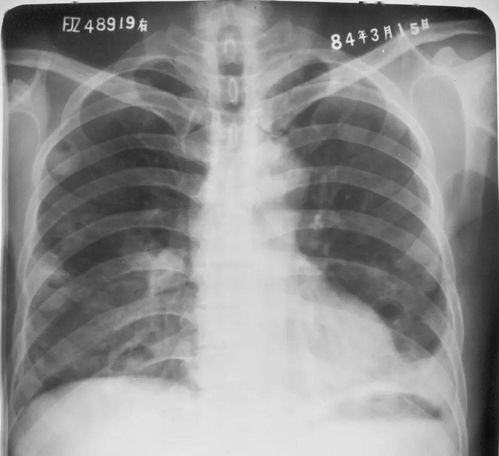

“胸片曝光”指的是使用X射线对患者胸部进行成像的过程,X射线是一种电磁辐射,能够穿透身体不同密度的组织,在胸片上,密度高的组织(如骨骼)会呈现为白色,密度较低的组织(如肺部,充满空气)呈现为黑色或深灰色,而中等密度的组织(如心脏、大血管、肝脏、脾脏等)则呈现为不同的灰度,通过观察这些影像信息,医生可以判断是否存在异常,如肺炎、肺结核、肺癌、心肌肥厚、胸腔积液、肺气肿、胸膜病变、骨骼异常等。

报告结论/诊断意见: 这是报告的核心部分,医生会根据影像学表现给出明确的描述和诊断意见。“心肺纹理清晰,双肺透亮度好,心影不大,膈肌升高,肋骨走行正常。” 或者 “右下肺野见片状密度增高影,考虑急性肺炎。” 报告中会明确指出发现的问题或异常。

影像学描述: 医生会用专业术语描述在胸片上看到的结构和异常表现。“斑片状阴影”、“结节影”、“索条影”、“胸腔积液征”、“主动脉弓增宽”等,理解这些描述有助于您了解异常的具体形态。

- 观察肺部: 正常肺野应该是深灰色(含气),如果看到大片白色或混杂区域,可能提示炎症、积液或纤维化,黑色区域如果异常扩大,可能提示肺气肿。

- 观察心脏和大血管: 心脏轮廓在胸片上大致呈“靴形”或“梨形”,如果心脏轮廓增大,可能提示心脏功能或结构问题,主动脉弓是胸片上重要的血管标志,增宽可能提示动脉瘤。

- 观察胸廓和骨骼: 肋骨、胸椎、锁骨等结构应排列整齐,无扭曲或异常增厚,胸腔内软组织密度均匀。